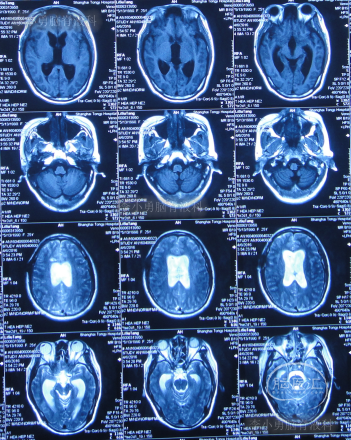

第三家医院第3次门诊图-1

图-1:2016年3月18日头颅CT